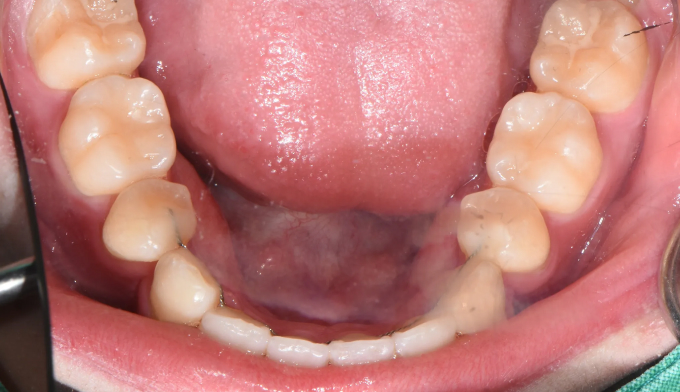

이가 배열될 공간이 부족해서 삐뚤빼뚤하게 나왔습니다.

가지런한 앞니는 성장중인 학생들에게 큰 자신감을 줍니다.

총 치료기간은 19개월 입니다.